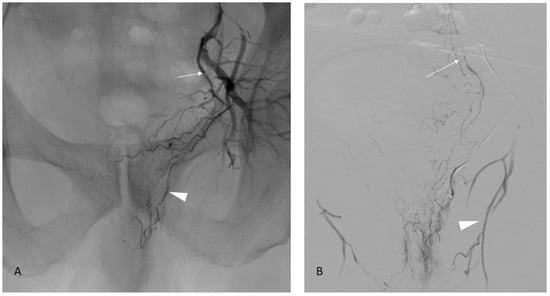

Collateral to the rectum (Figure 5, middle rectal branch, 14%) or bladder (inferior bladder arteries, 11%) are frequent situations [13]. If the prostatic branches can be catheterized supraselectively, these can be embolized directly. If supraselective embolization is not feasible, the middle rectal or lower bladder branch must be occluded using a microcoil, which redirects the flow to the prostatic artery.

Figure 5.

Prostate artery connection with the middle rectal artery. Image (A): Iliac angiography demonstrating a vesico-prostatic trunk (arrow) with collateral in the direction of the rectum (arrowhead). Image (B): Supraselective angiography in the middle rectal artery confirming the opacification of the rectum and connection with the superior rectal artery (arrow) arising from the inferior mesenteric artery. Note another shunt with the obturator artery (arrowhead).